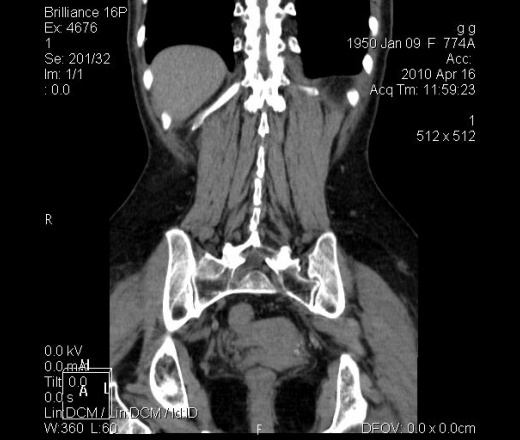

Не увидел желчного и селезенки..почки 2 поджелудочная 1 , мочевой есть..и самое главное я не разбираюсь вКТ

Не хватает желчного и селезенки.

Лишний поясничный позвонок, к тому же 1 поясничный - с передней клиновидной деформацией.

Желудок удалён, думаю. Селезёнка, скорей всего тоже, во всяком случае, выглядит атипично.

С кишками без контраста туго.... Левое 12 ребро короче, но это может быть вариант. Th12 клиновиден. Есть левосторонний сколиоз на этом уровне.... костная структура Th11 неравномерно уплотнена (?), остеохондроз Th10-11-12.

ЭКСПЕРТИЗА с целью обратить внимание на серому. Дело в том, что мне они еще не попадались. Может, у кого-то в архиве есть подобные изменения? Поделитесь, пожалуйста!

а я ткогда смотрел заметил только что нету селезенки и желчного :) То что нету желудка не расмотрел. УУУУ!!!!

Биломы после резекции сегментов печени видел, а вот сером после спленэктомии никогда не видел! Когда смотрел исследоваие, то думал о поддиафргамальном абсцессе слева (конечнор надо учитвать клинику). А так писал бы про осумкованнгое поддиафрагмальное скоплдение содержимого однородного характера (если бы была соответствующапя колинрика добавил бы выражение "!поддиафрагмальный абсцесс?")

а левая доля печени где? мне кажется её тоже не хватает